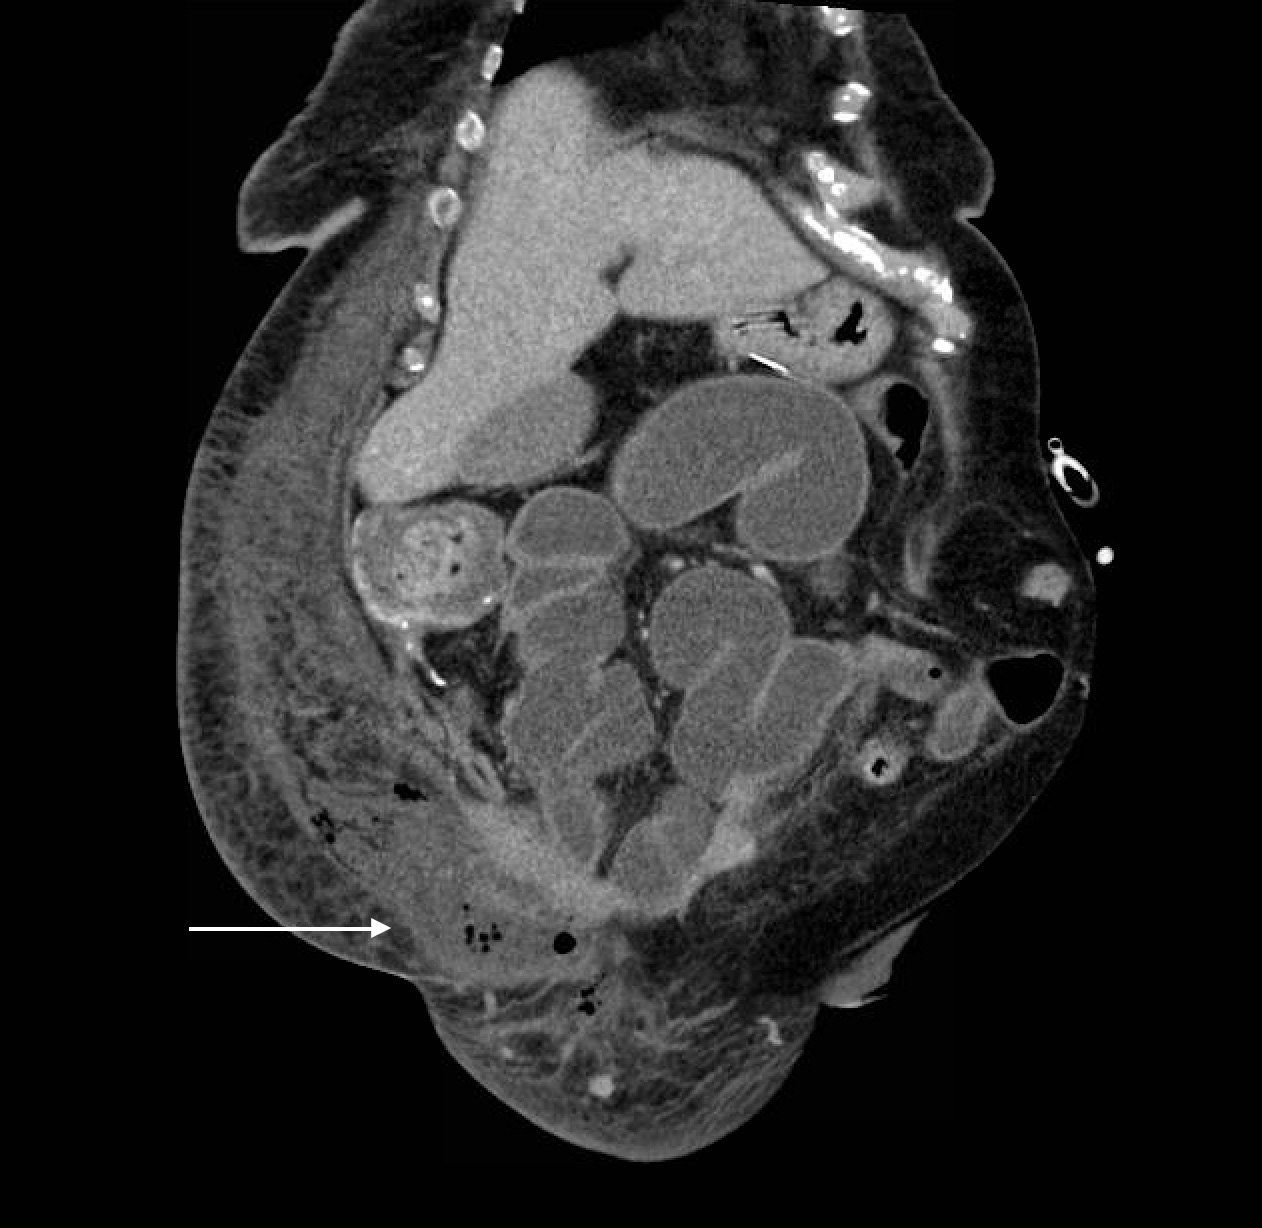

Computed tomography (CT) of the abdominal and pelvis with intravenous (IV) contrast revealed inflammatory changes, including gas and fluid collections within the ventral abdominal wall extending to the vulva, consistent with a necrotizing soft tissue infection.